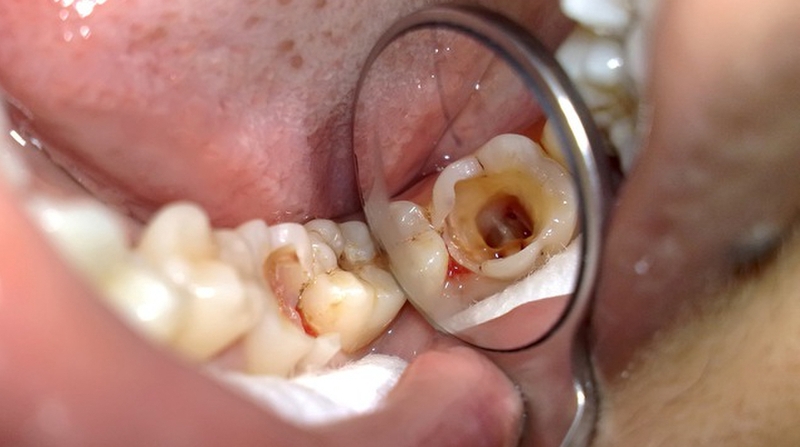

Sâu răng

Khi đeo niềng răng, bạn sẽ vệ sinh răng khó hơn bình thường vì bàn chải đánh răng không thể chạm vào các ngóc ngách giữa các răng do mắc cài. Do đó, dễ tích tụ mảng bám gây sâu răng. Bạn nên vệ sinh răng miệng 2 lần/ngày và dùng bàn chải kẽ răng. Bạn cũng có thể cân nhắc sử dụng tăm nước để làm sạch răng hơn.